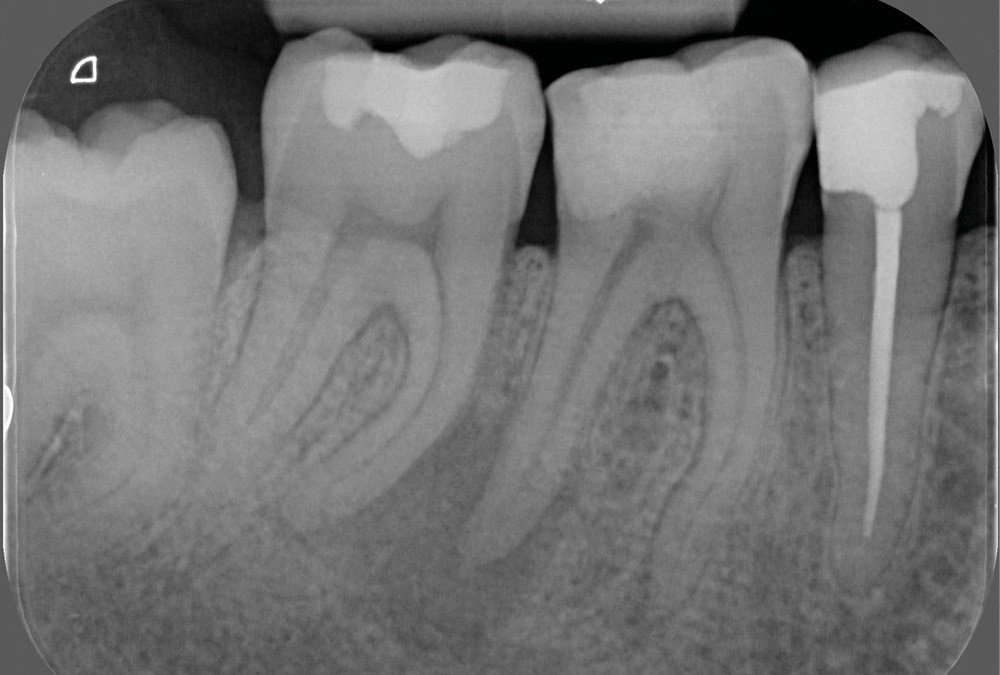

La préparation mécanique est principalement réalisée à l’aide d’instruments NiTi utilisés en rotation continue ou en réciprocité selon une approche corono-apicale. La mise en forme est ainsi plus rapide et respecte mieux le trajet canalaire initial qu’avec une instrumentation manuelle. Le diamètre apical et la conicité de la préparation canalaire font toujours débat. Ils dépendent de l’anatomie initiale et doivent permettre une irrigation efficace sans fragiliser la dent. Ainsi, un diamètre apical de 30 et une conicité de 6 % sont souvent proposés comme objectif minimal à atteindre [3] (fig. 1).